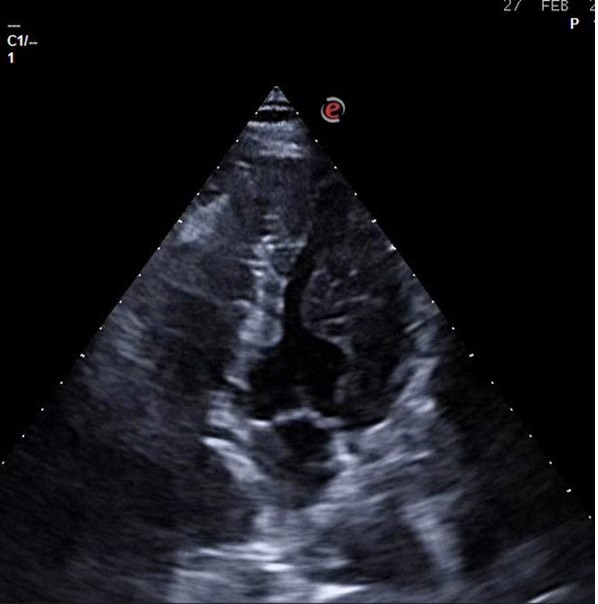

En nuestro centro se le realizó Ecocardioscopia: En eje paraesternal largo se observa grosor parietal aumentado más a nivel septal y de predominio en septo basal donde alcanza los 18 mm. VI no dilatado. FEVI conservada. No alteración de la contractilidad ni valvulopatías.

En primera instancia se sospechaba de Miocardiopatía hipertrófica o por depósitos. Cuando se concluyó el estudio se diagnosticó al paciente de un miocardio con trabéculas paraseptales prominentes.